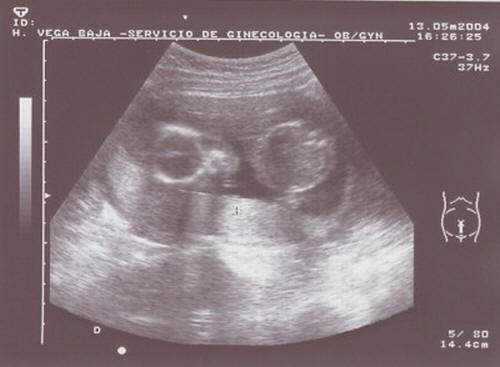

News flash....... baby update!!!!! Here's my latest photo (taken at 17 weeks old), and this time I thought I'd give you a full frontal view. The circle on the left is my head and if you look carefully you can see my eye sockets and little nose. The circle on the right is my belly, I may look a bit tubby, but I've just had my lunch! Mummy, Daddy and I have had a very busy time recently.............the other Friday we went to see the midwife, as I was waiting for a blood test and scan. The following Monday morning we went to hospital to do the scan and blood test. The scan didn't take too long, but we had a long wait for the blood test so Daddy bribed a police officer to swap his appointment, which was earlier than ours, for 20 euros....well done Daddy, nothing ventured nothing gained! On Thursday we went to Orihuela for a more detailed scan, and then back there again the next morning for another blood test. Poor Mummy, she'll have no blood left if they keep this up! Tomorrow morning, Monday, we're off to hospital again as the Obstetrician wants a chat about the blood test results of last week. We are all a bit worried, but will just have to wait and see what he says. We're gonna see the midwife on Tuesday, and I think Mummy will be weighed!!! But she is being very careful what she eats and I think that the midwife will be happy with her. We have another appointment for blood test results at the end of May and a scan booked in June, before our trip to the UK. Gosh, how popular do I feel...... I'm still not very big, just big enough to fit in the palm of your hand. So I've a long way to go yet. I'm kicking away and getting my exercise but Mummy can't feel me yet.... maybe this will have changed by the time I write next. Keep in touch and I'll up date you again soon. Lots of love to you all. Tom       x x